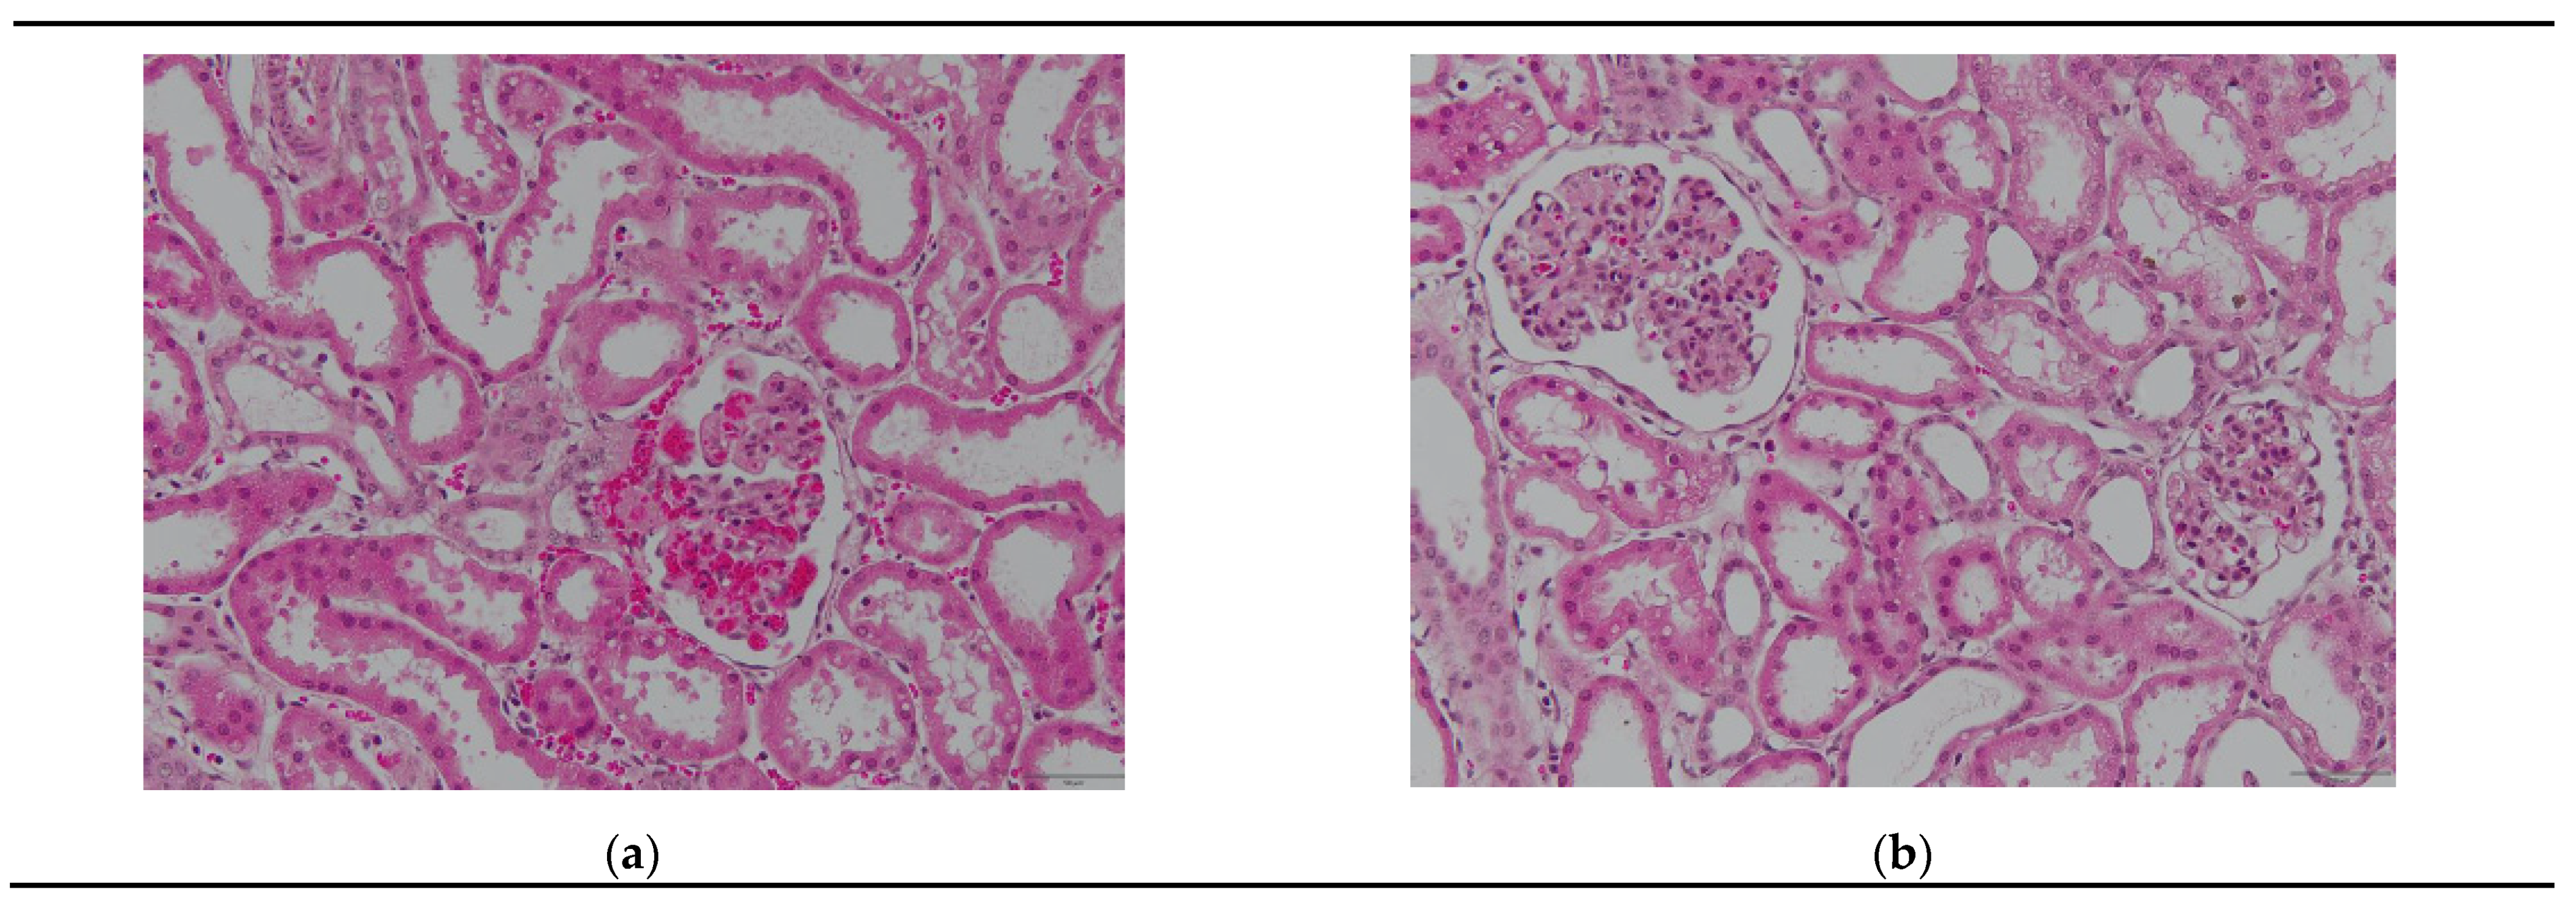

3.2.1. Hematoxylin–Eosin Staining

3.2.2. ERG and CD42b Immunohistochemistry